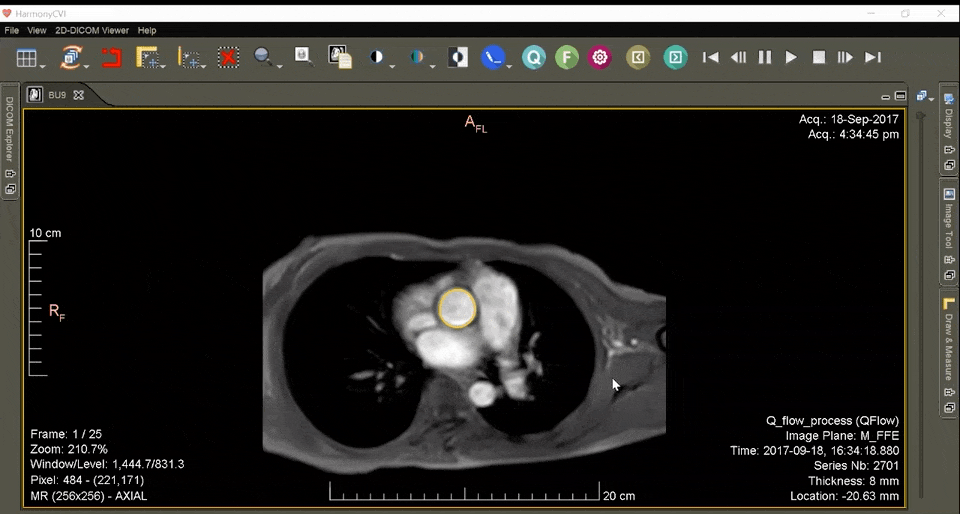

Our flagship HarmonyCVI TM is an image post-processing analysis software system that enables detailed visualization & quantification of cardiovascular MRI

Our flagship HarmonyCVI TM is an advanced comprehensive AI-based platform for Automatic Analysis of the Cardiac MRI scans for Accurate Diagnosis & Insights in a quick time